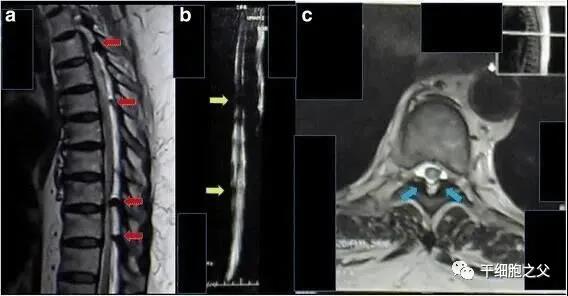

2017年海外报道一例62岁的印尼籍妇女,被诊断为胸部截瘫、慢性肾功能衰竭、糖尿病,长期肾脏受累,慢性肾功能衰竭2年,肌酐水平为11mg/dL,无小便。

采用间充质干细胞移植方案治疗。鞘内注射1.6×107个间充质干细胞,静脉注射1.6×107个间充质干细胞。

△ 患者胸部磁共振成像显示,脊髓受到多处压迫

临床结果:鞘内注射和静脉注射三周后,患者可以移动脚趾,肾功能得到改善。肌酐水平降至9 mg/dL。8个月后,患者可以抬起腿,肌酐水平是2mg/dL,小便恢复正常。